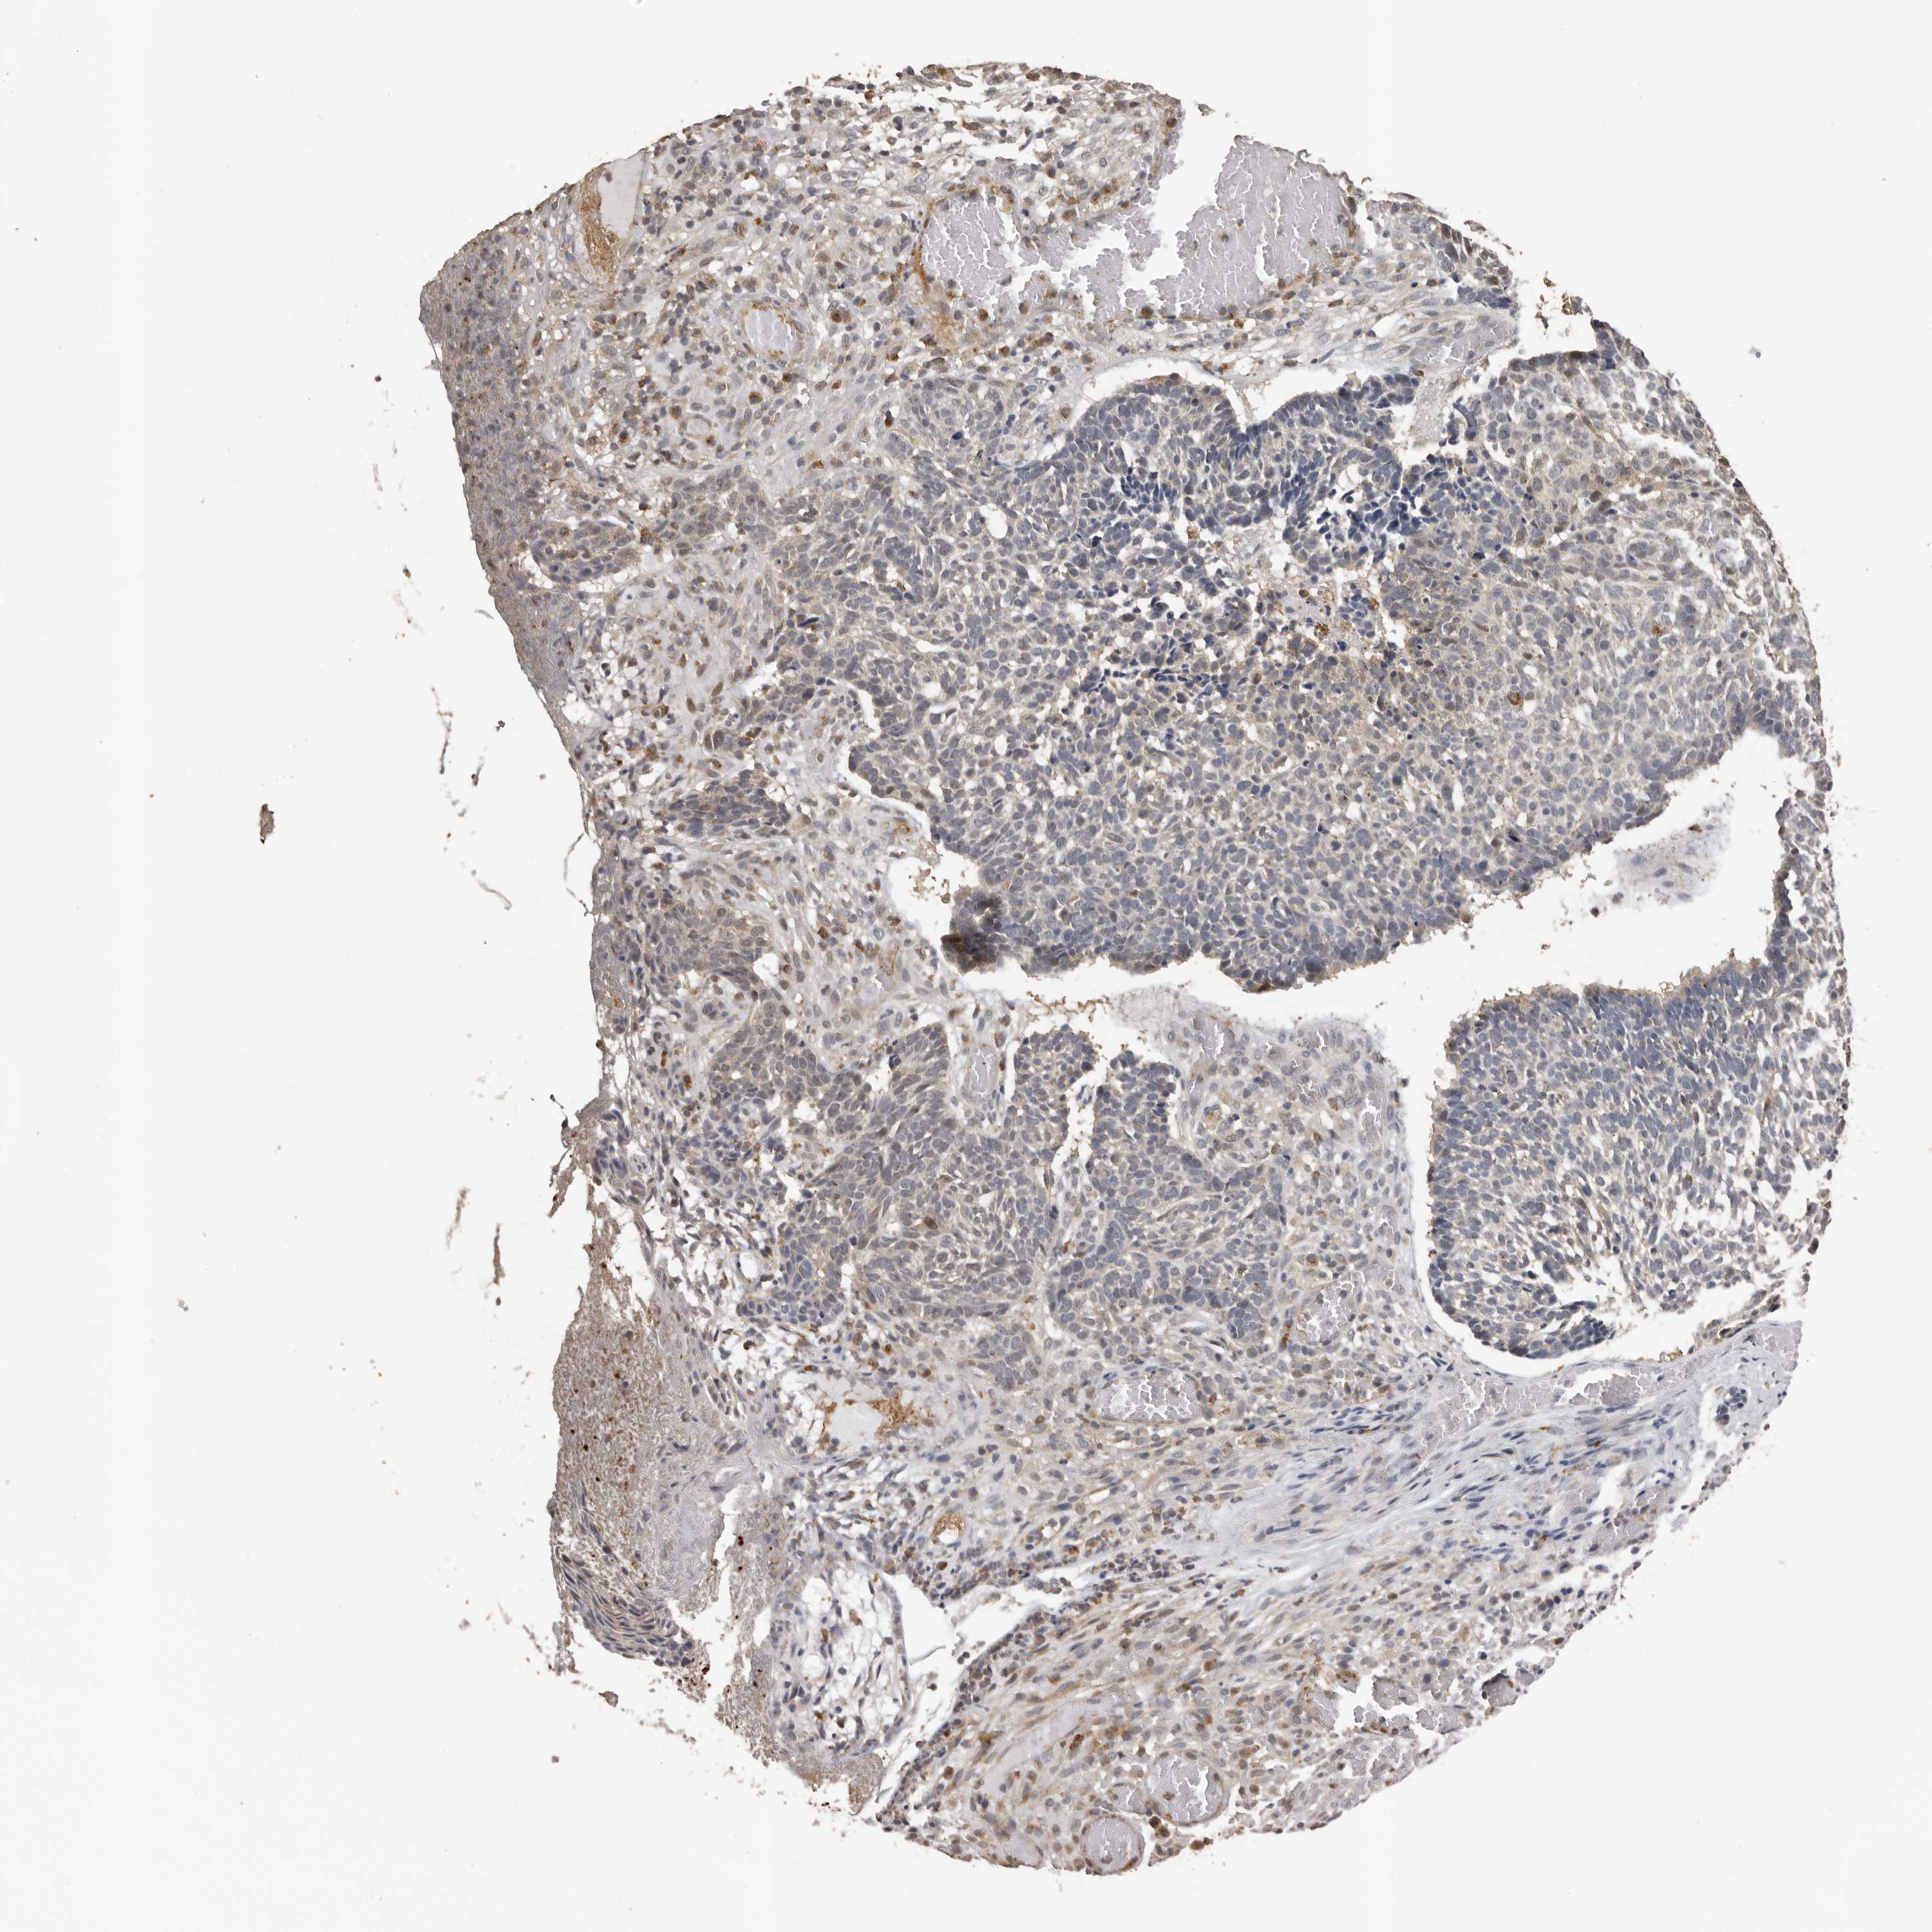

Basal cell and squamous cell cancer

SKIN CANCER - Protein expressioni

A mouse-over function shows sample information and annotation data. Click on an image to view it in a full screen mode. Samples can be filtered based on level of antibody staining by selecting one or several of the following categories: high, medium, low and not detected. The assay and annotation is described here.

Each image is clickable and will lead to virtual microscopy that enables deeper exploration of all samples and also displays staining intensity scores, fraction scores and subcellular localization as well as patient and tissue information for each sample.

Antibody HPA024795

Squamous cell carcinoma, NOS